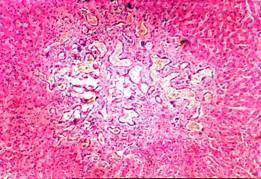

A subsequent chest radiograph showed complete resolution of shadowing. Routine blood tests, including liver function, were completely normal. An abdominal ultrasound scan (figure 1) showed multiple echo poor lesions and a CT scan of the abdomen (figure 2) showed multiple low attenuating lesions suggesting metastatic liver disease. A liver biopsy (figure 3) under ultrasound guidance showed cystically dilated bile ducts lined with flat and cubical epithelial cells, surrounded by a fibrous stroma, consistent with a diagnosis of multiple bile duct hamartomas or von Meyenburg complexes.

Figure3. A liver biopsy showing cystically dilated bile ducts lined with flat and cubical epithelial cells, surrounded by a fibrous stroma

Von Meyenburg complexes (VMCs) are believed to be ductal plate malformations of the smallest intrahepatic bile ducts due to disordered embryonic involution [1, 2]. Macroscopically, VMCs of the liver present as grey-white nodular lesions scattered throughout the liver parenchyma, usually measuring between one and ten millimeters in diameter [3].Microscopically, they are generally cystically dilated bile ducts lined by a single layer of cuboidal cells and embedded in a fibrocollagenous stroma [4].